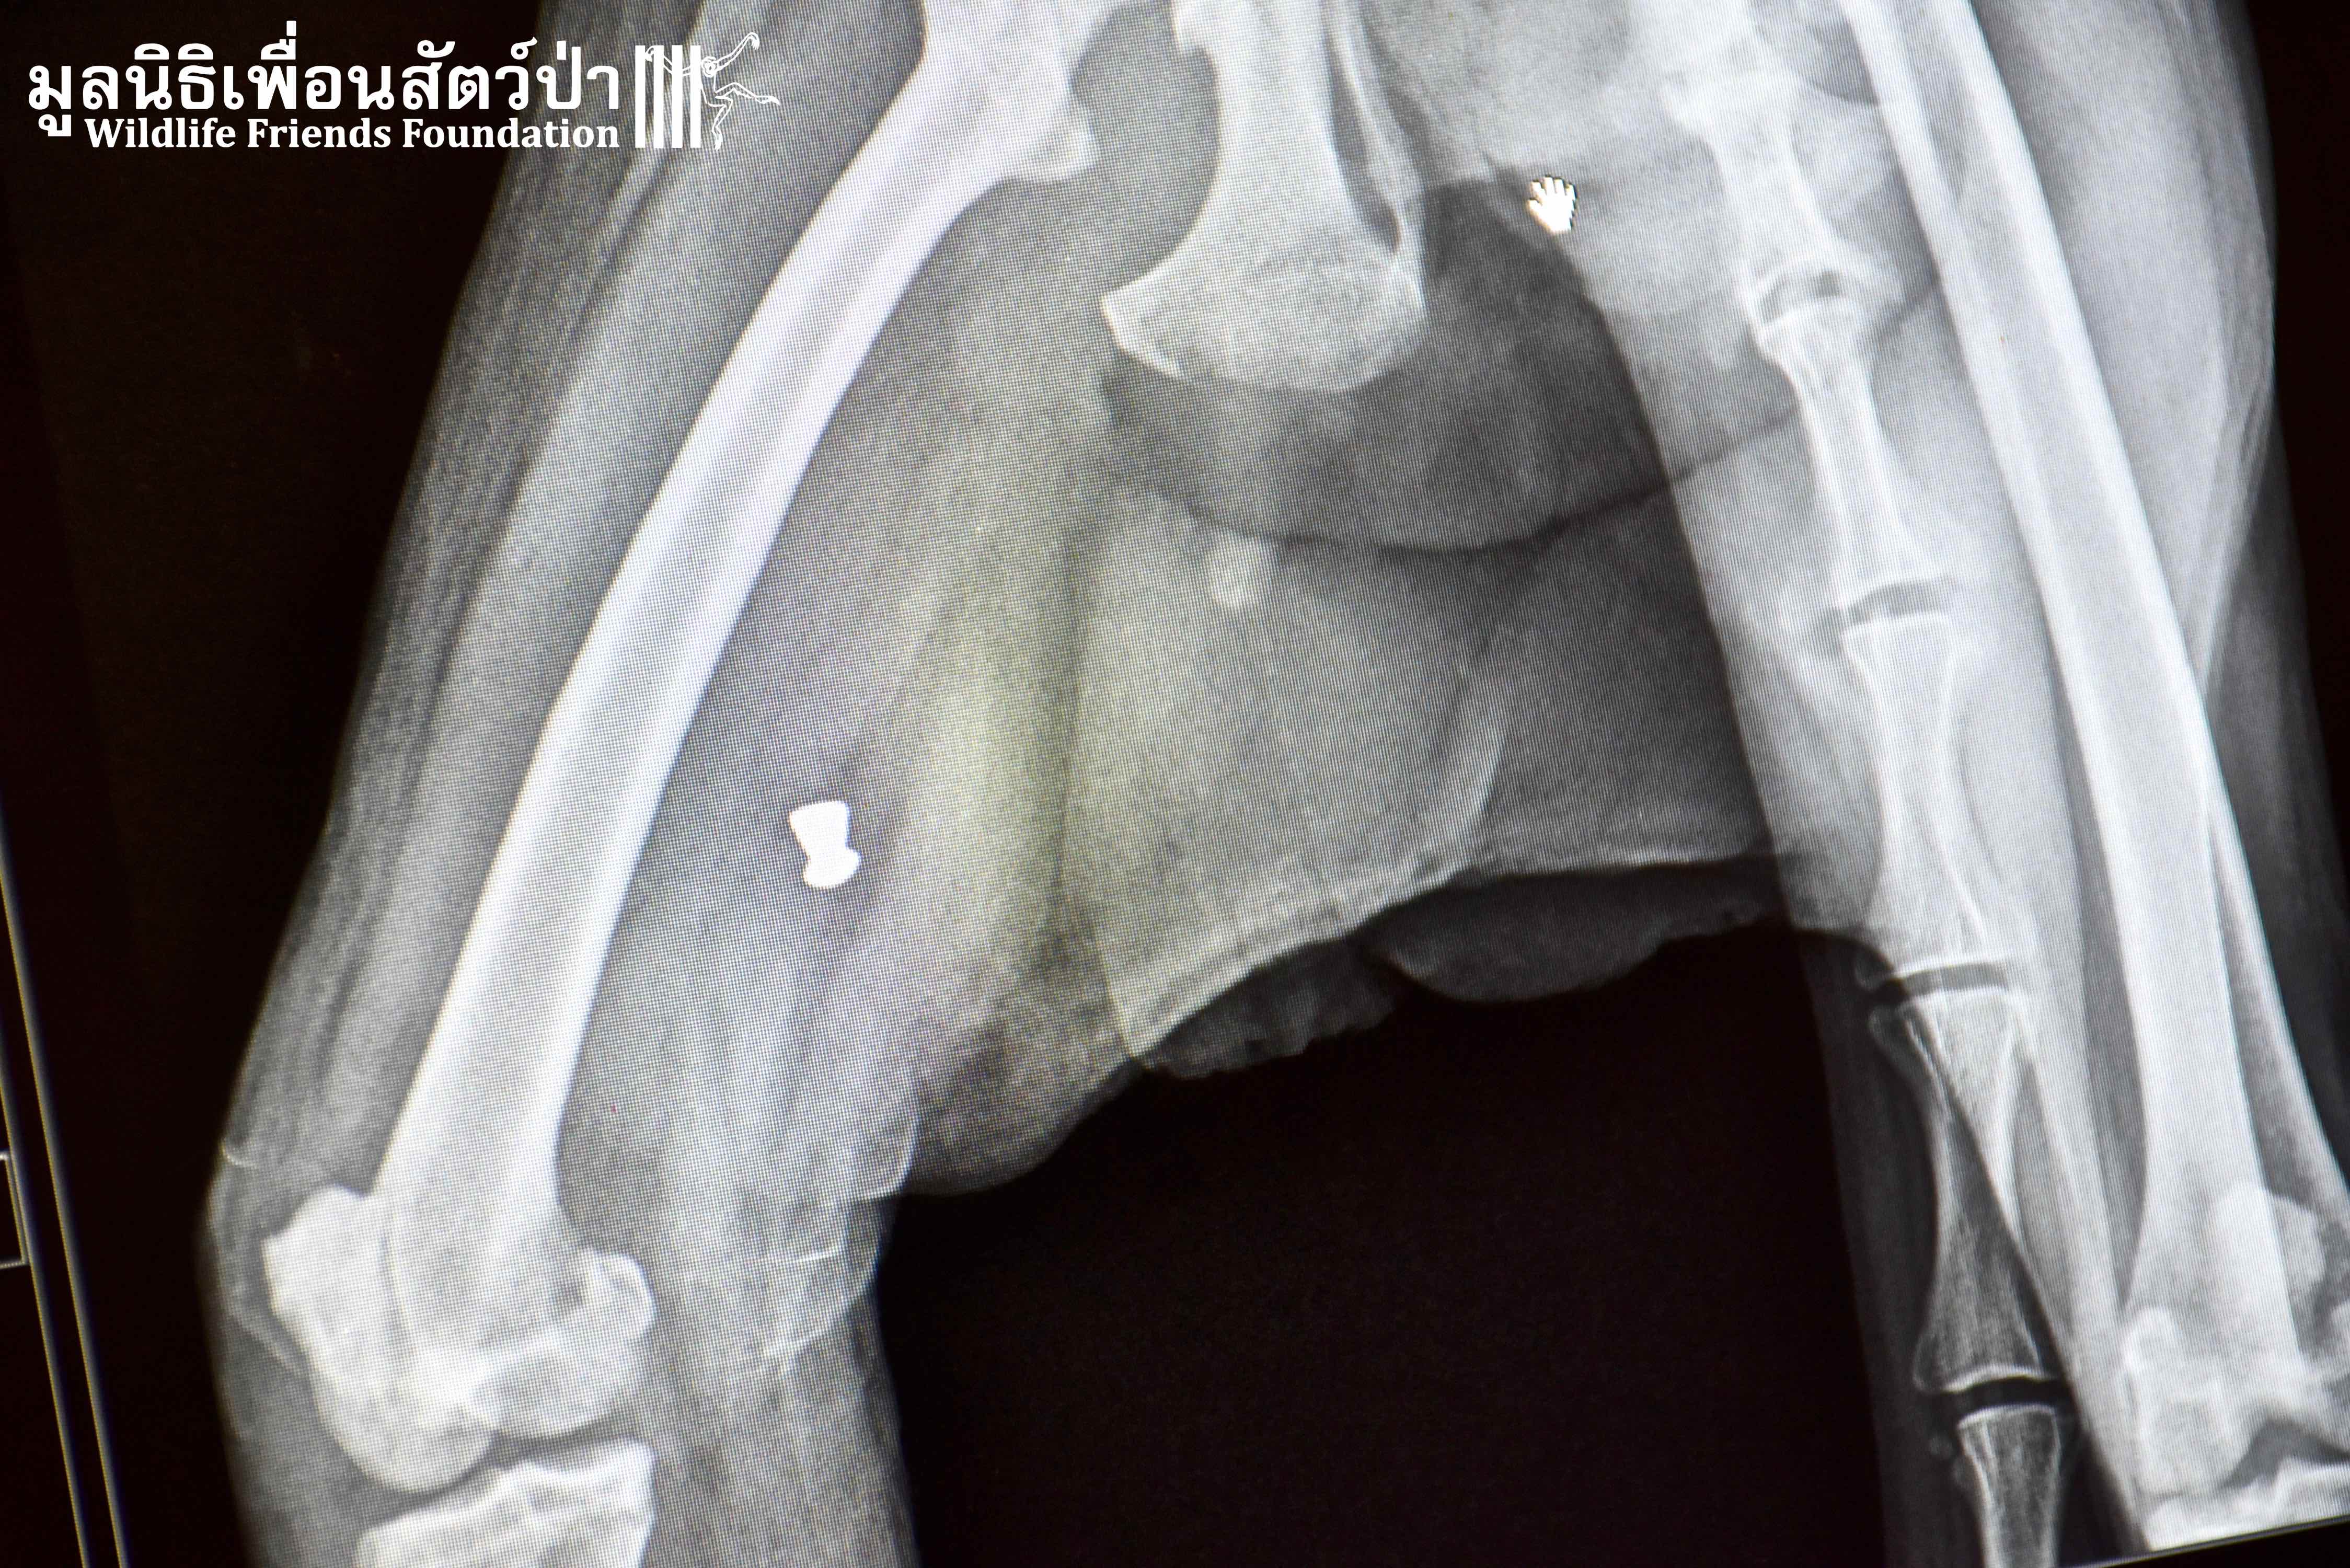

It was raining long-tailed macaques (Macaca fascicularis) in the hospital this week! Our first patient, Auan, arrived 2 months ago after being hit by a car. Although no breaks or dislocations were found, his radiographs revealed four old bullets lodged in his spine, thigh, ankle, and arm. His right leg suffered additional extensive abrasions from the car accident. Our hospital staff surmise that he has nerve damage that led to him painlessly dragging around his disabled limb, thus getting it infected. We decided to amputate this leg to avoid further complications. Because he is a large adult male, we are hopeful that he can be successfully released after he recovers and passes observation in quarantine.

Our second amputation of the day was of another long-tailed macaque, Bucky, who first came to us several months ago after falling out of a tree. He belongs to an urban macaque troop that is fed by a local community in Bangkok. They trapped and brought him to WFFT after noticing he had stopped using his arm. Once again, no breaks or dislocations were found in his radiographs but a fresh bullet wound was discovered in his disabled arm. It was removed and he was returned to his troop. However, he was brought back to WFFT this week because he still wasn’t using his arm. To avoid future risks of injury and sepsis, this arm was amputated after Auan’s leg amputation. After his recovery he will be returned to his troop in Bang Khun Thian, Bangkok.